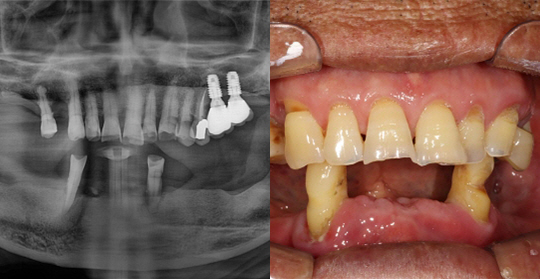

(50세 남 환자)